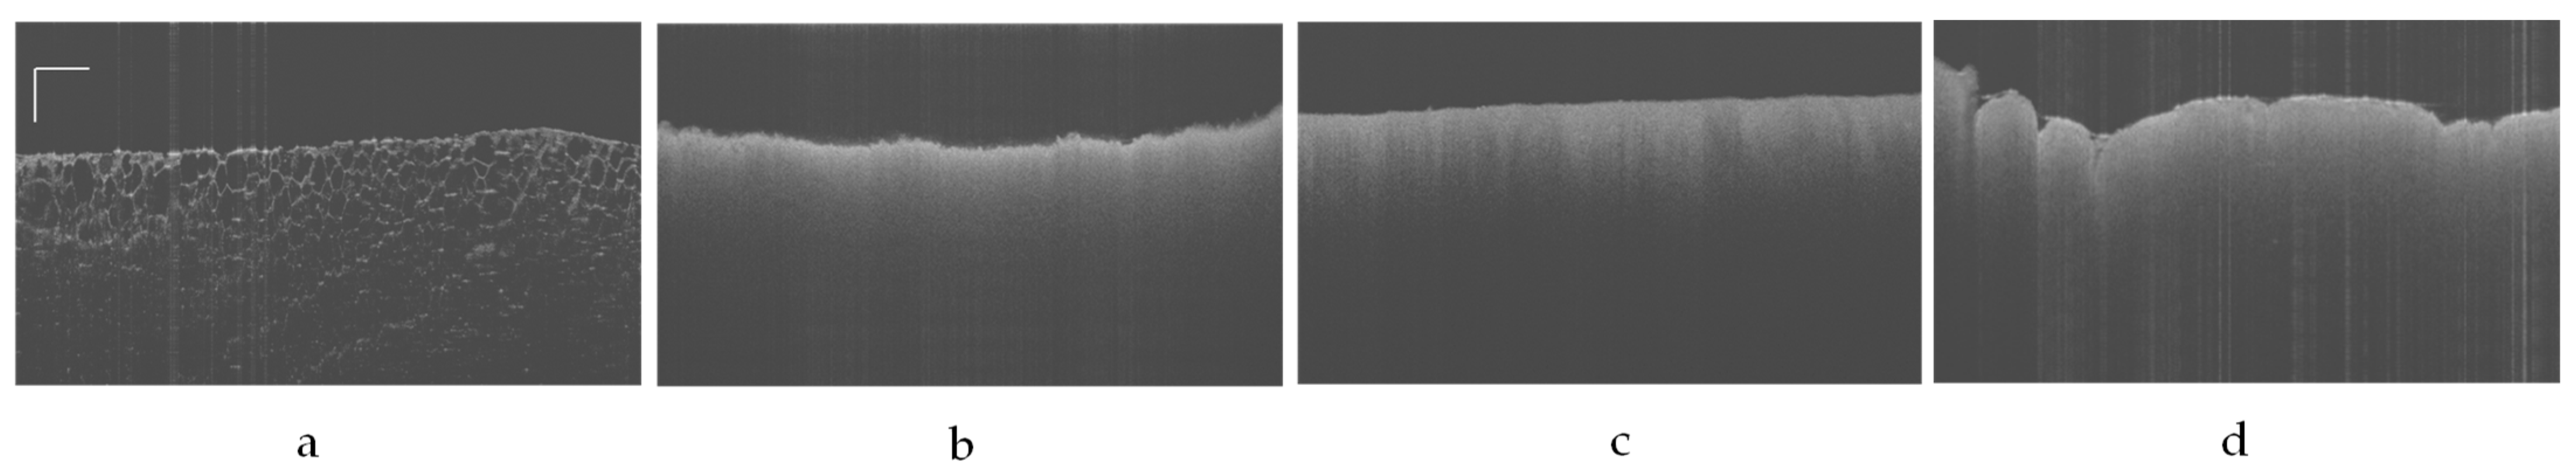

3.1. OCT